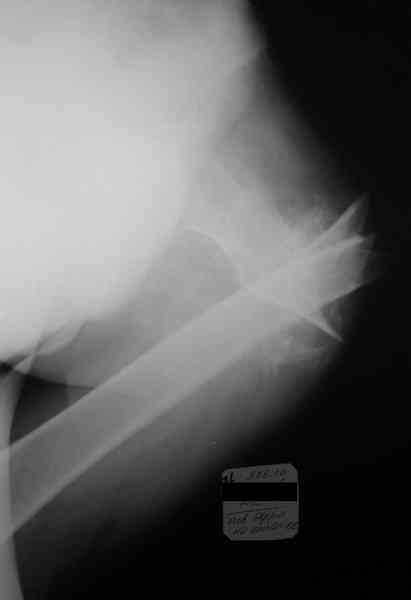

Re: Неправильно консолидирующийся перелом бедра